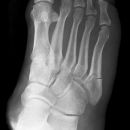

Lisfranc Luxationsfraktur